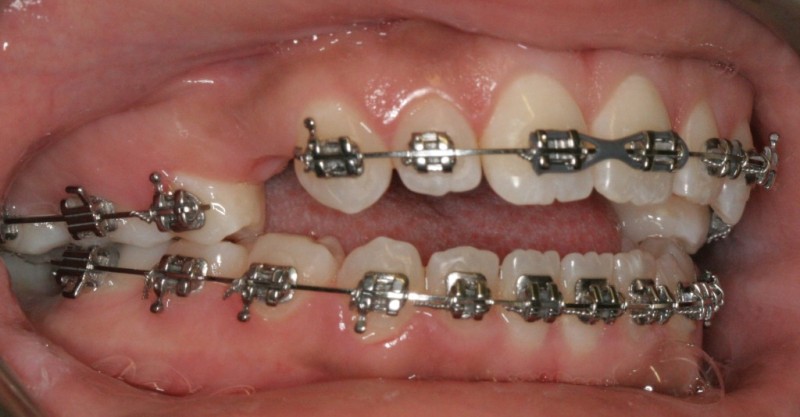

After Orthodontic Setup - Presurgical